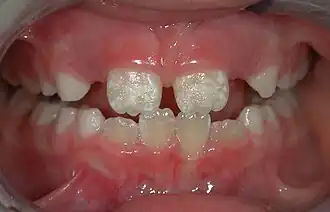

Irreversible enamel defects caused by an untreated celiac disease. They may be the only clue to its diagnosis, even in absence of gastrointestinal symptoms, but are often confused with fluorosis, tetracycline discoloration, or other causes.[50][51][52] The National Institutes of Health include a dental exam in the diagnostic protocol of celiac disease.[50]

Some groups have spoken out against fluoridated drinking water, for reasons such as the neurotoxicity of fluoride or the damage fluoride can do as fluorosis. Fluorosis is a condition resulting from the overexposure to fluoride, especially between the ages of 6 months and 5 years, and appears as mottled enamel.[3] Consequently, the teeth look unsightly, although the incidence of dental decay in those teeth is very small. Where fluoride is found naturally in high concentrations, filters are often used to decrease the amount of fluoride in water. For this reason, codes have been developed by dental professionals to limit the amount of fluoride a person should take.[38] These codes are supported by the American Dental Association and the American Academy of Pediatric Dentistry.

Fluorosis leads to mottled enamel and occurs from overexposure to fluoride.[27]